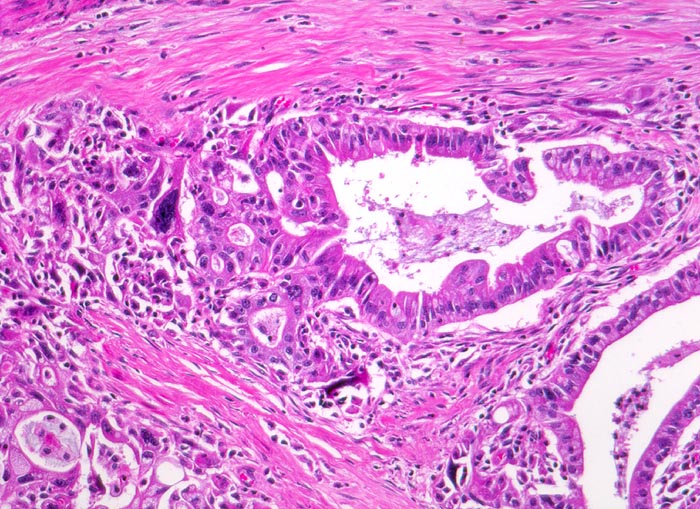

duktales Adenokarzinom des Pankreas

Teils kribriforme Tumordrüsen mit ausgeprägten Zellatypien und Kerngrössenschwankungen. Ein Teil der Drüsenlumina enthält nekrotische Tumorzellen. Die Tumorinfiltrate liegen eingebettet in reichlich desmoplastisches Stroma.

Unscharf begrenzter weisser derber Herd im Pankreaskopfbereich. Stenosierung und praestenotische Dilatation von Ductus choledochus und Pankreasgang vor der Papille.

Zunehmender schmerzloser Ikterus. Sonographische Darstellung einer 4cm grossen echoarmen Raumforderung im Pankreaskopfbereich. Dilatation des Pankreasganges und des Ductus choledochus. Whipple Operation.

125